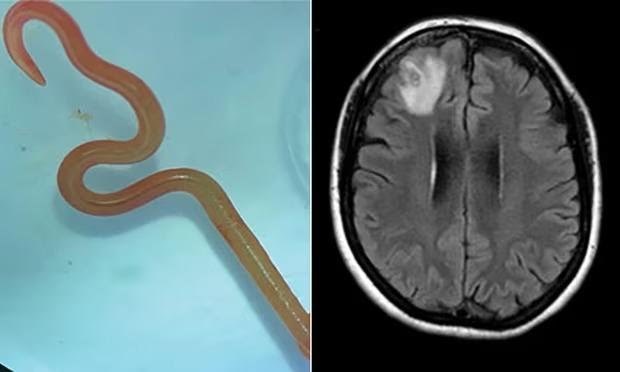

Os médicos encontraram uma lesão no lobo frontal direito, durante uma ressonância magnética. Quando a biopsia foi realizada, encontraram o verme, de cerca de 8cm. A região onde a paciente mora é habitada pelas cobras Pítons, comuns na Austrália.